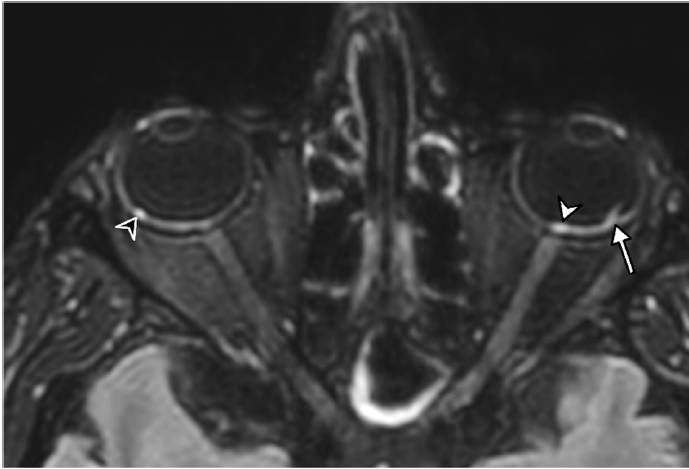

Identification of facial nerves impacted by this condition increases dramatically with DCE-MRI.